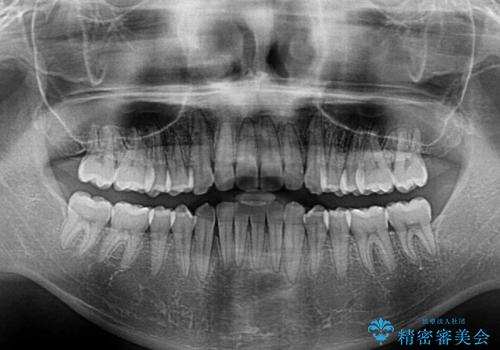

上下ともに歯列の幅が狭かったため、側方に拡大することで前歯のデコボコや突出感を解消するためのスペースを獲得することができました。

歯並びが改善したことはもちろん、咬み合わせの改善まで実感することができ、患者様には大変満足していただけました。